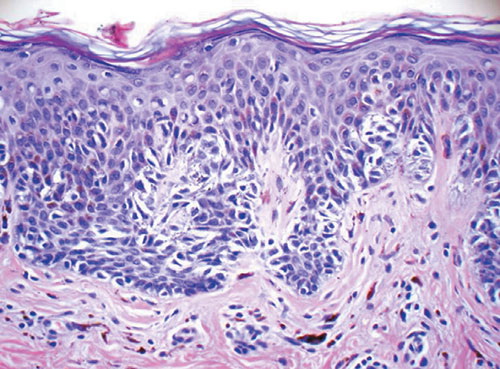

Atypical compound (dysplastic) nevus =وحمة مركبة عسيرة التصنع غيرنموذجية